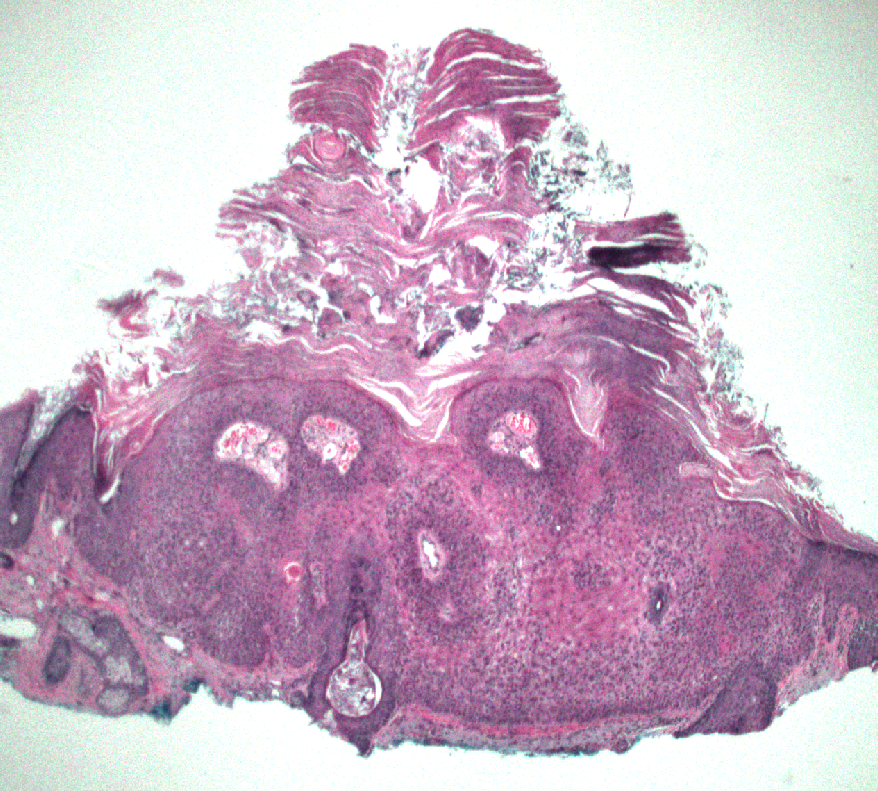

40 F. 10 cm deep thigh mass.

Answer ✅ youtu.be/QDb68_G1HR4?si…

Digital slide 🔬 kikoxp.com/posts/11800.

Differential dx: kikoxp.com/posts/12124

#BSTpath #pathologists #pathology #pathTwitter